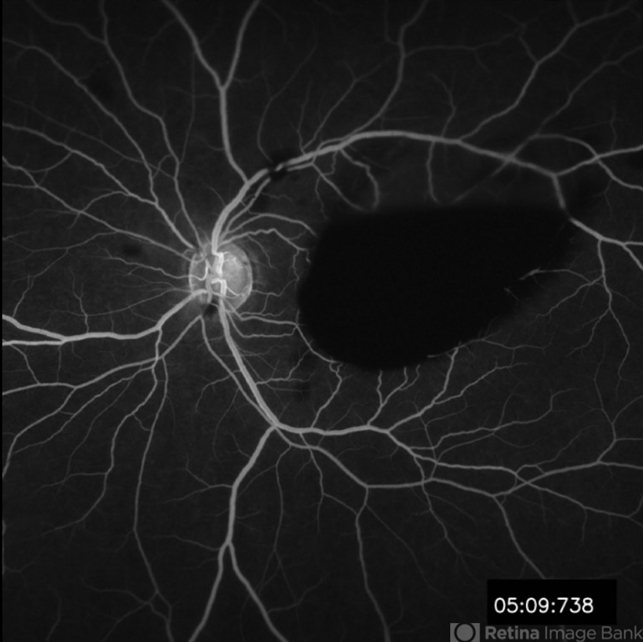

valsalva retinopathy, fundus photograph, fluorescein angiogram (FA)

These photos depict the fundus photo and corresponding fluorescein angiogram for a 43 year old man with emesis after food poisoning. Note the blockage from the central preretinal hemorrhage and scattered peripheral intraretinal hemorrhages.